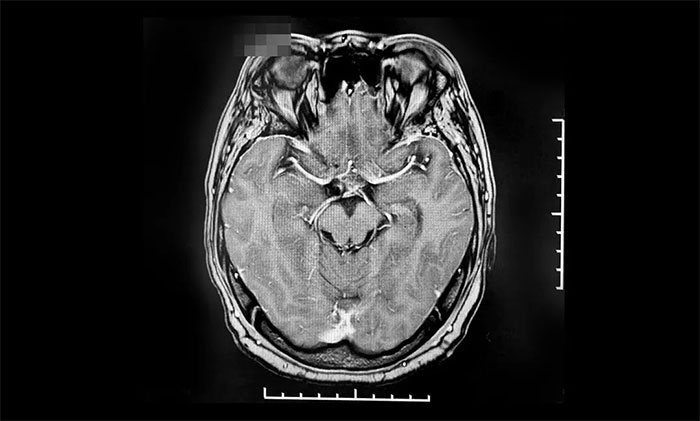

▲ 腫瘤復(fù)發(fā)后,來(lái)我院行伽瑪?shù)吨委熐坝跋?/font>

2022年8月,因視力下降就醫(yī),復(fù)查提示腫瘤復(fù)發(fā),遂來(lái)上海藍(lán)十字腦科醫(yī)院進(jìn)行伽瑪?shù)吨委,后順利出院。今?0月,患者來(lái)院復(fù)查,影像學(xué)檢查提示腫瘤體積較治療前明顯縮小,患者視力較前改善,控制良好,陳琦主任叮囑其繼續(xù)隨訪觀察。